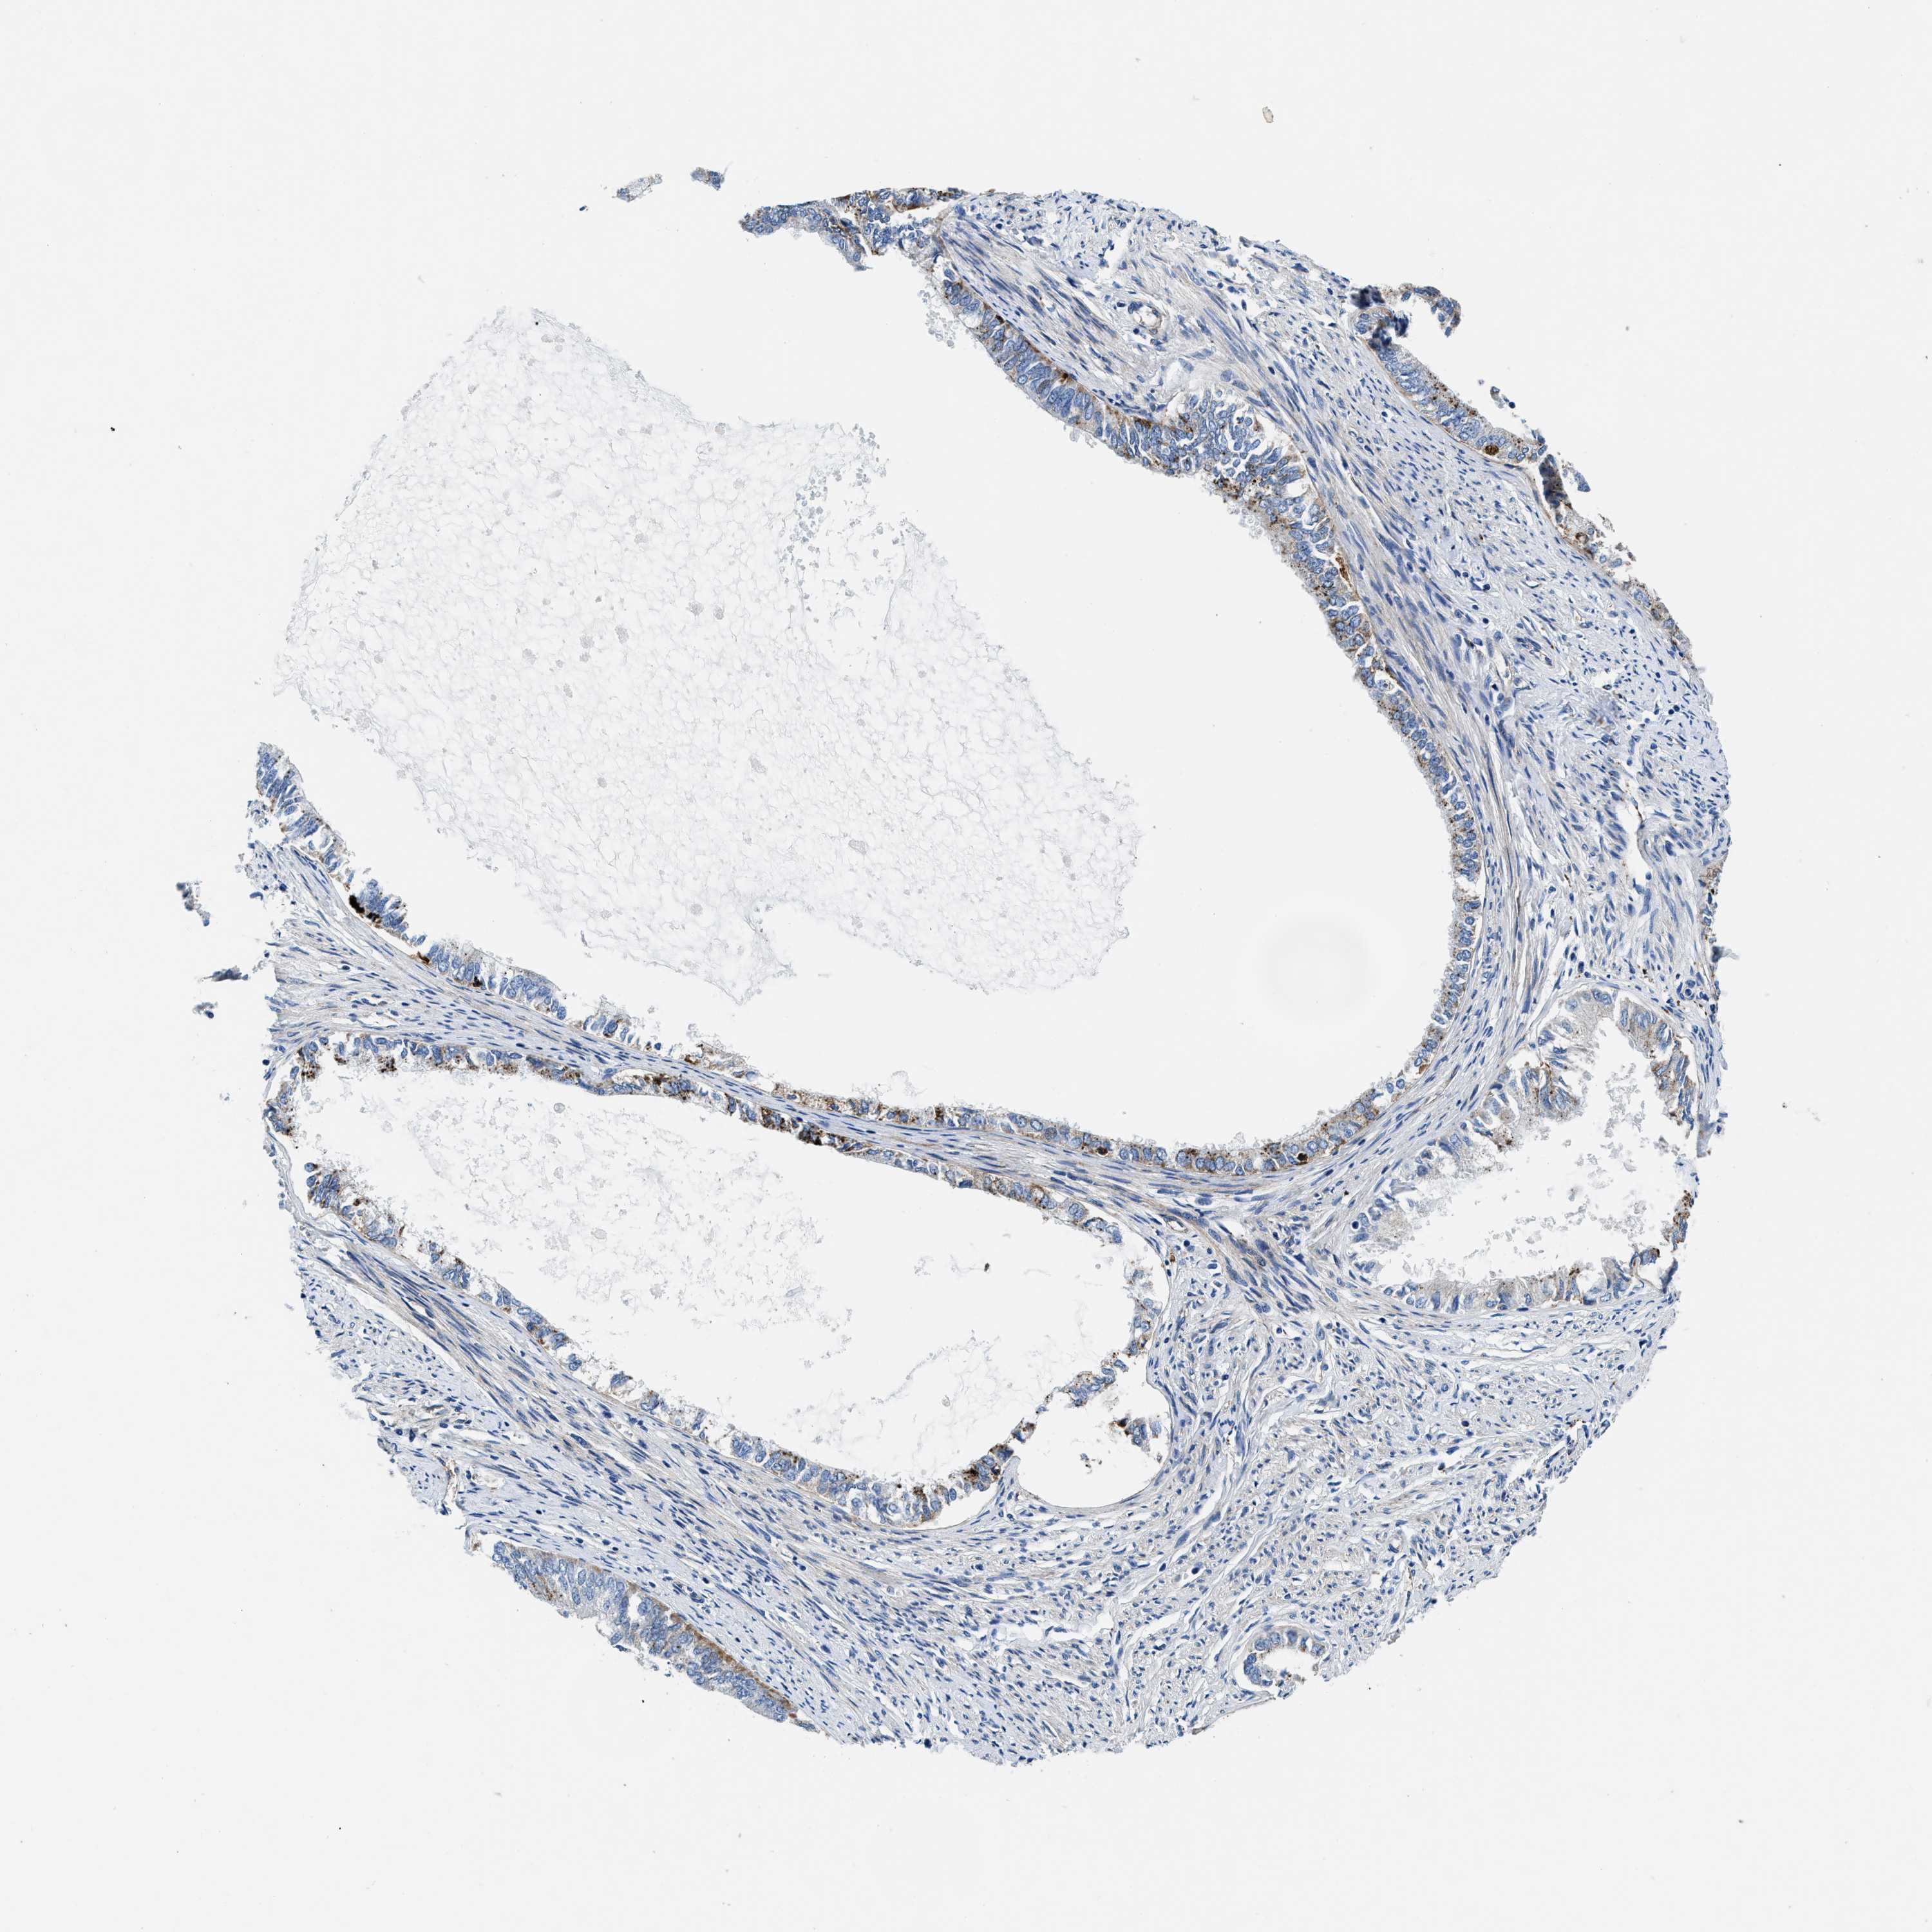

ENDOMETRIAL CANCER - Protein expressioni

A mouse-over function shows sample information and annotation data. Click on an image to view it in a full screen mode. Samples can be filtered based on level of antibody staining by selecting one or several of the following categories: high, medium, low and not detected. The assay and annotation is described here.

Note that samples used for immunohistochemistry by the Human Protein Atlas do not correspond to samples in the TCGA dataset.

Antibody stainingi

Antibody staining in the annotated cell types in the current human tissue is reported as not detected, low, medium, or high, based on conventional immunohistochemistry profiling in selected tissues. This score is based on the combination of the staining intensity and fraction of stained cells.

Each image is clickable and will lead to virtual microscopy that enables deeper exploration of all samples and also displays staining intensity scores, fraction scores and subcellular localization as well as patient and tissue information for each sample.

Antibody CAB001960

Antibody CAB016353

Staining

High

Medium

Low

Not detected

Intensity

Strong

Moderate

Weak

Negative

Quantity

>75%

75%-25%

<25%

None

Location

Nuclear

Cytoplasmic/membranous

Cytoplasmic/membranous,nuclear

Adenocarcinoma, NOS